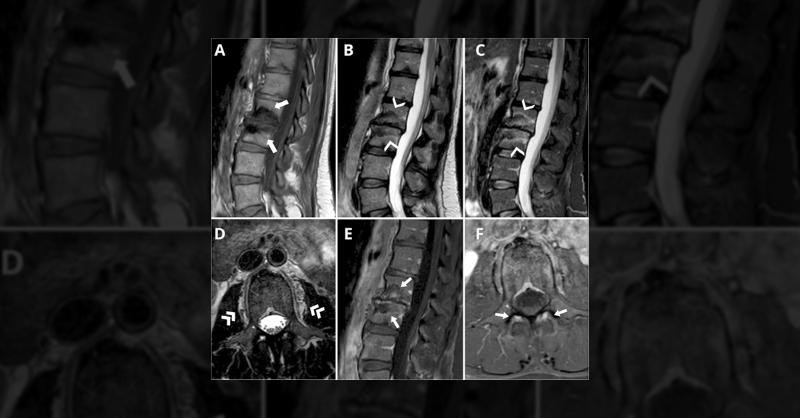

A 44-year-old woman with a 35-year history of type 1 diabetes presented with two months of lumbar pain, night sweats, and difficulty maintaining an erect posture. Physical examination revealed discrete trunk forward-leaning. Initial blood tests showed hyperglycemia and decreased renal function. Lumbar MRI revealed signal intensity changes in both a